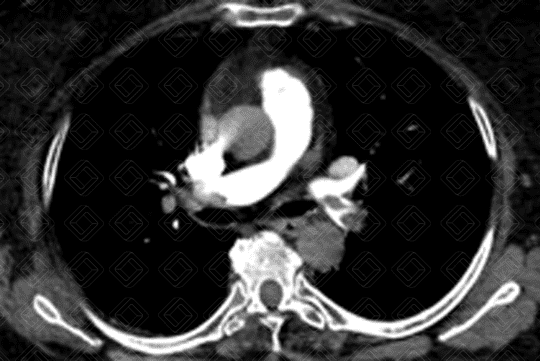

Descrição das imagens: Angiotomografia computadorizada do tórax com aquisições axiais e coronal, evidenciando tromboembolia pulmonar maciça com “êmbolo em sela” (seta vermelha) nas artérias pulmonares principais.

• Angiotomografia computadorizada do tórax: Padrão-ouro para o manejo do TEP agudo. Este exame é sempre realizado após a administração do meio de contraste. O principal sinal é a falha de enchimento, formando um ângulo agudo com a parede do vaso, delimitada pela substância contrastante (figura 1).